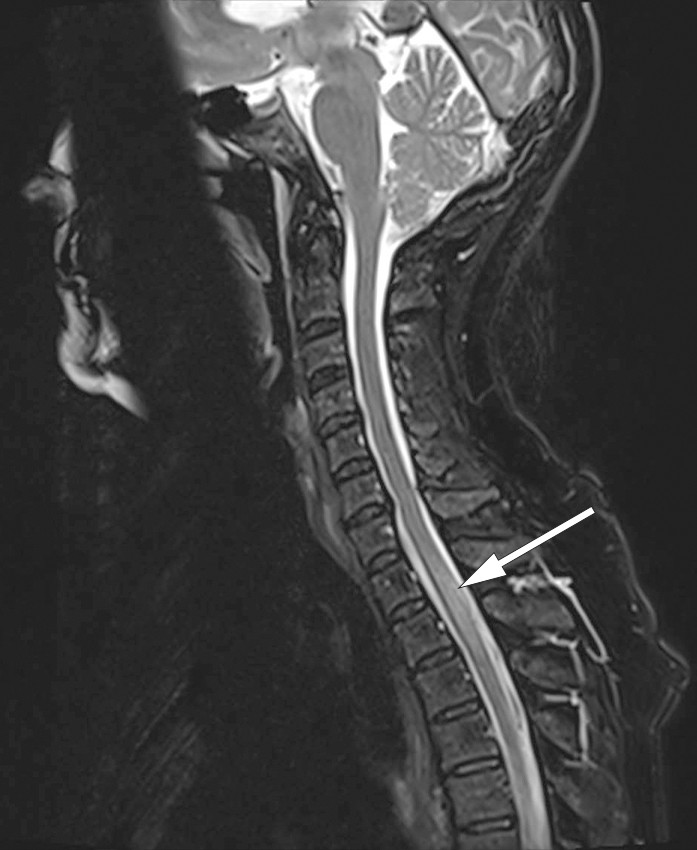

Man gjorde derfor kontrastforsterket MR-undersøkelse av medulla, som viste nytilkomne intramedullære forandringer forenlige med myelitt og meningitt (figur 2 og 3). På dette tidspunktet hadde det tilkommet diskrete trunkale sensoriske forstyrrelser og lett hyperrefleksi i underekstremitetene.